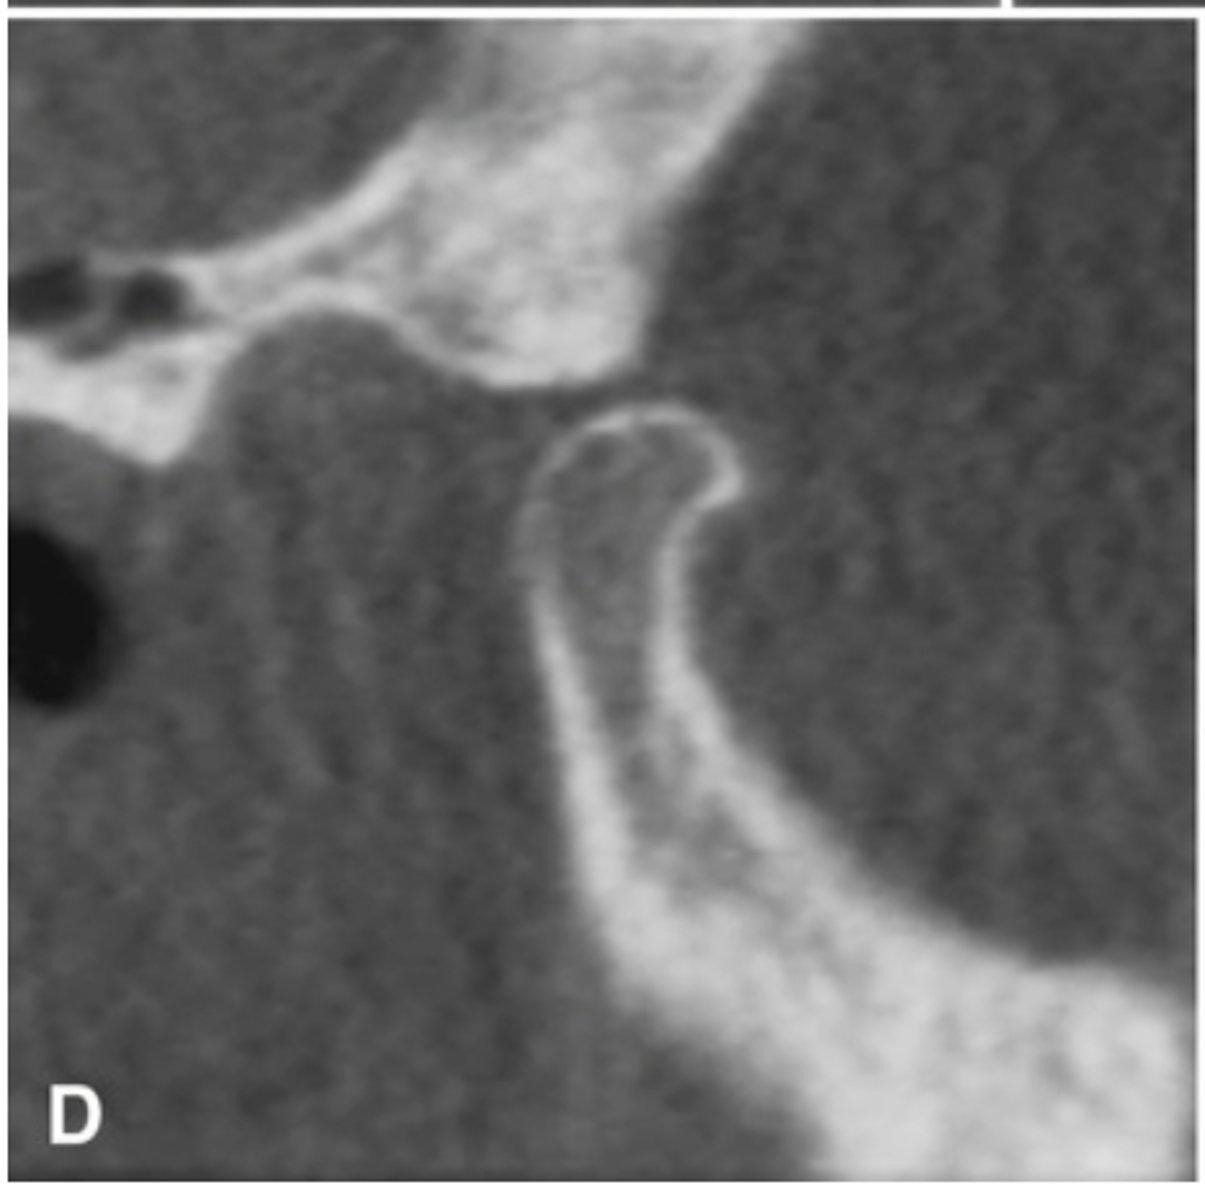

Bifid condyle

- Vertical depression in the condylar head

- often unilateral but may be bilateral

- may be a result of trauma

- some patients may have TMJ dysfunction

- Treatment isn't indicated unless pain or fxn impairment.

What is this developmental abnormality, and what is the etiology for it?